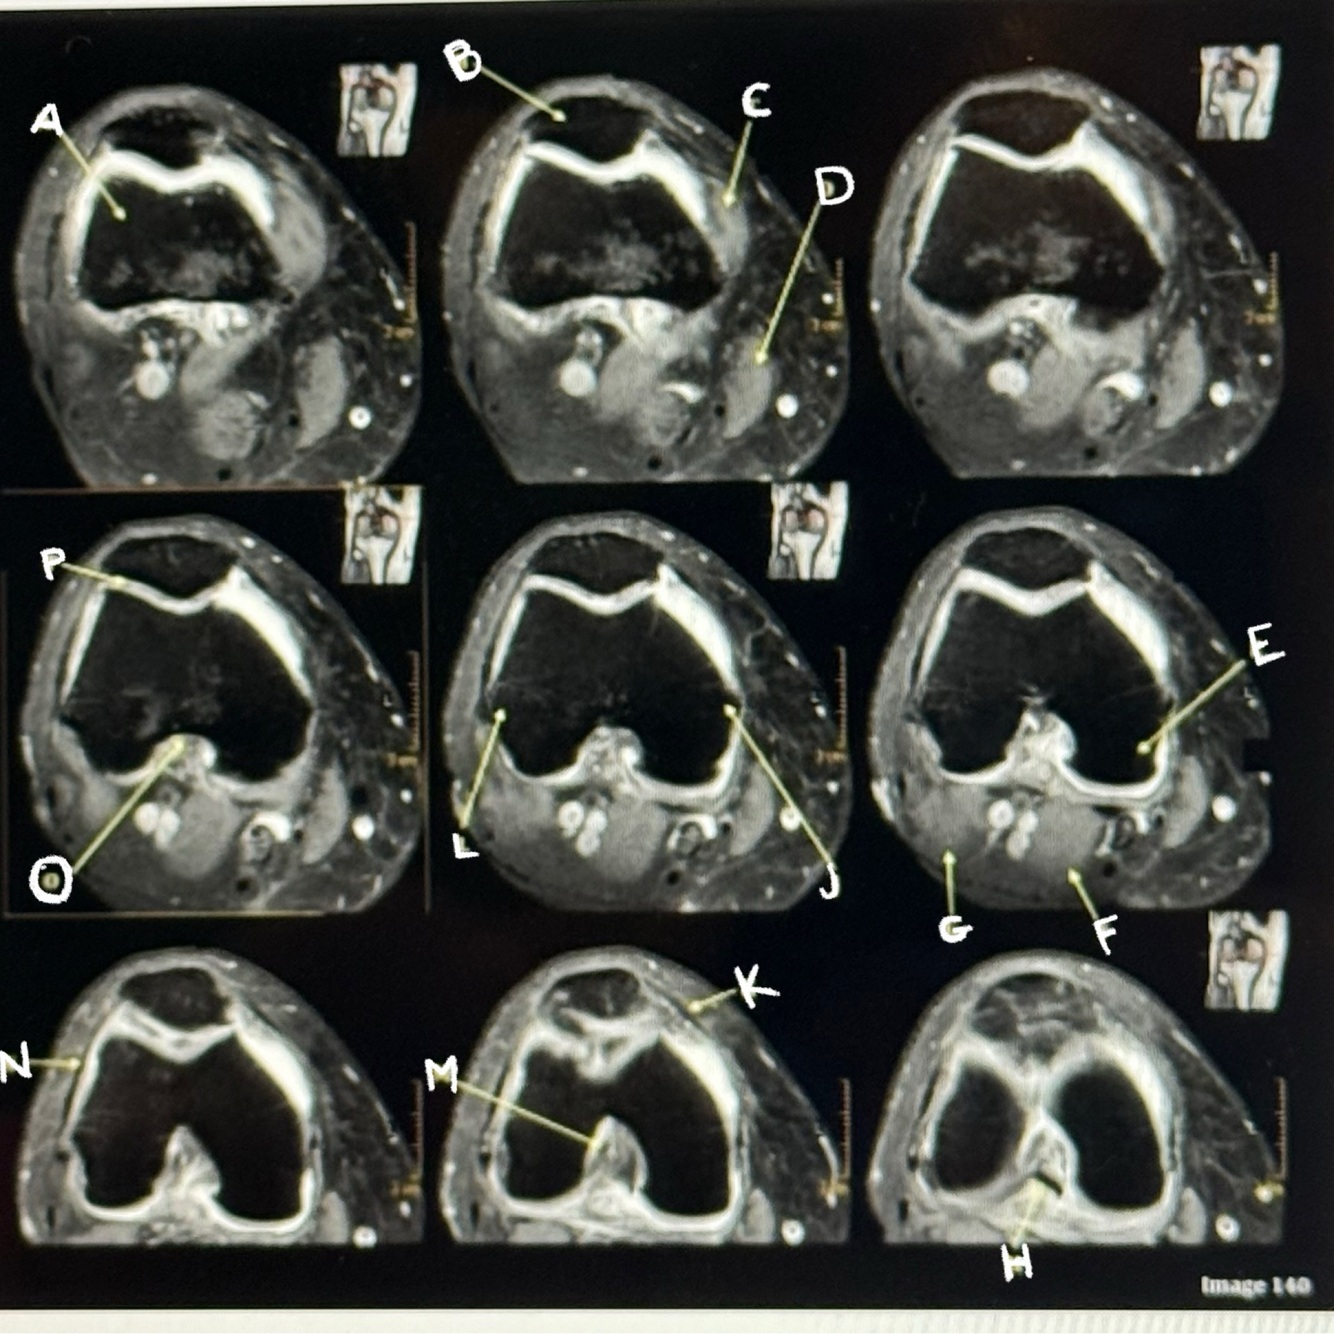

Letter P points to the

Articular cartilage

39

Letter M points to the

Anterior cruciate ligament

40

Letter N points to the

Lateral retinaculum

41

Letter O points to the

Intercondylar fossa

42

Letter K points to the

Medial retinaculum

43

Letter L points to the

Lateral epicondyle

44

Letter H points to the

Posterior cruciate ligament (PCL)

45

Letter D points to the

Sartorius muscle

46

Letter C points to the

Vastus medialis muscle